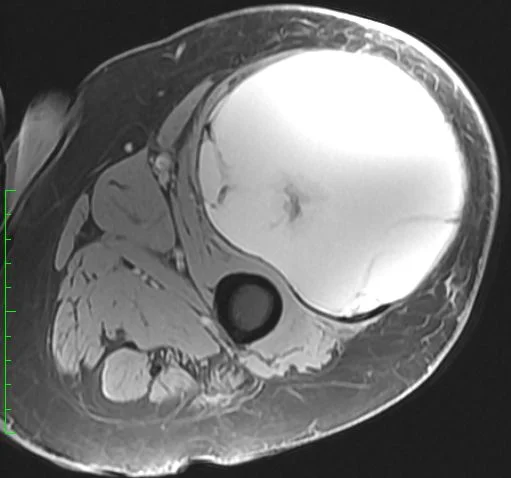

This 62 year old man presented with thigh pain and swelling. MRI imaging showed a large mass within the quadriceps muscle (vastus lateralis). Biopsy was performed at the time of initial evaluation and confirmed a high grade undifferentiated sarcoma. The tumor was localized to the thigh (Stage III).

He completed 5 weeks of preoperative radiation and then underwent surgery. Below are MRI images of his tumor. The first image below shows the change in the tumor before and after radiation. It is not uncommon for sarcomas to enlarge during radiation therapy. This is thought to be due to cell death from radiation resulting in hemorrhage

The next two images above show the extent of the tumor at the time of surgery. The last image demonstrates how most of the mass is fluid and blood, as the large bulk of the mass does not take up contrast and remains dark.